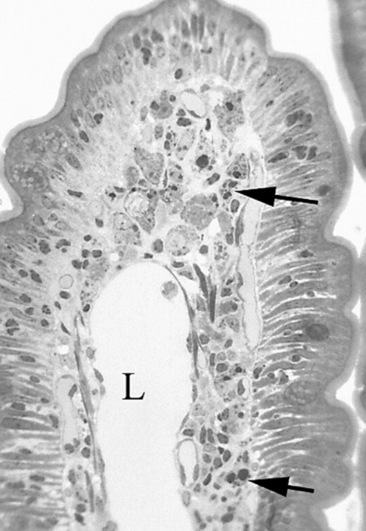

Ultrasound evaluation of horses with abdominal pain (colic) provides a rapid method to identify abnormalities within the gastrointestinal tract. Distention of the small intestine to a diameter greater than 5 cm has been strongly associated with strangulating or obstructing lesions19 (Fig. 32-11). In foals with intussusception, the small intestine appears enlarged and there is generally distended small intestine orad to the lesion; however, at the site of the intussusception there is a normal-appearing small intestinal wall (intussuscipiens) surrounded by a larger structure that appears to surround the inner small intestinal wall (called the intussusceptum)19 (Fig. 32-12). Large colon torsion occurs when the large colon rotates 360 degrees or more around the root of the mesentery to cause occlusion of venous drainage while maintaining arterial flow. This causes the wall to become thick and edematous. If ultrasound is performed in the cranioventral abdomen, just caudal to the xiphoid process, then a colon wall size greater than 9 mm is 100% specific for a large colon torsion21 (Fig. 32-13). A large colon displacement would have minimal to no vascular compromise, so it would be an ultrasound diagnosis based on exclusion. Chronic displacements did have a mild amount of edema in the colon wall, causing the size to be approximately 7 mm thick but never greater than 9 mm in the one study described.21 The colon and small intestinal wall will also become thick with inflammation. Small intestinal wall thickness greater than 4 mm is indicative of inflammation.19 The right dorsal colon can be imaged in the right tenth to twelfth intercostal space around the region of the costochondral junction, and a focal wall thickness of 9 to 12 mm has been identified with right dorsal colitis.23